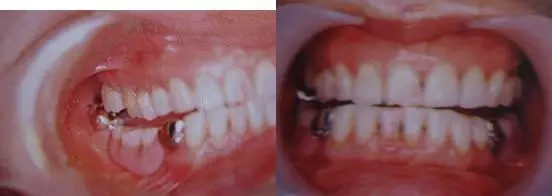

圖9. 上頜和下頜第二磨牙中發(fā)生的前方誘導干擾引發(fā)的張口困難。

下頜磨牙的遠中頰側牙尖的近中頰側斜面和上頜磨牙的近中頰側牙尖的遠中腭側斜面相接觸。

圖10. 不考慮下頜第三磨牙的咬合平面破壞的修復體制作完成后,后方磨牙干擾引發(fā)的前方誘導干擾。